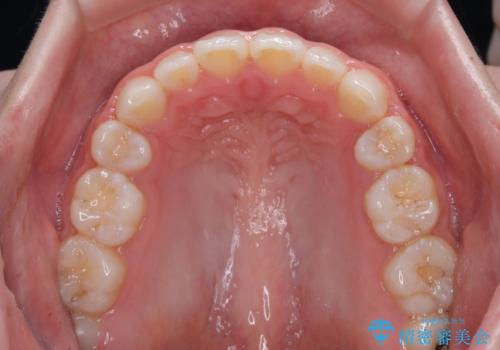

- 前歯が開いて飛び出していることを気にして来院された患者様です。

舌の突出癖により上下前歯は接触できず、更には前方に押し出されて出っ歯になっている状態でした。

上下左右の第一小臼歯4本を抜歯し、ワイヤー装置での抜歯矯正を行っていくのですが、原因である舌の突出癖を改善しないことには治療がうまく進められないため、舌のトレーニングを徹底するよう指導していくこととしました。